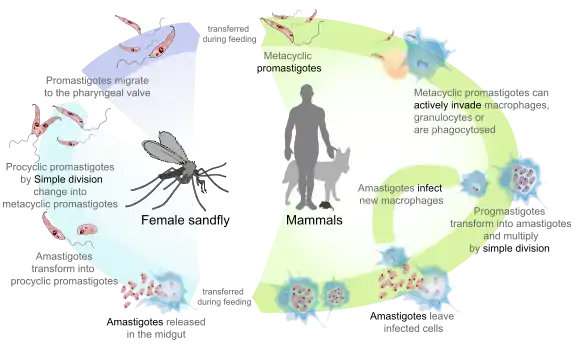

Leishmaniasis

The three forms of leishmaniasis are visceral (Kala-azar), cutaneous, and mucocutaneous.[40] There are an estimated 12 million people infected.[15] It is fatal if untreated and 20,000 deaths from visceral leishmaniasis occur annually.[41] It is a vector-borne disease that is caused by the bite of sandflies.[25] At least 90 percent of visceral leishmaniasis occurs in Bangladesh, Brazil, Ethiopia, India, South Sudan, and Sudan. Cutaneous leishmaniasis occurs in Afghanistan, Algeria, Brazil, Colombia, Iran, Pakistan, Peru, Saudi Arabia, and Syria. Around 90 percent of mucocutaneous leishmaniasis occurs in Bolivia, Brazil, and Peru.[40]

The only method of prevention is a vaccine that is under development and prevention of sandfly bites. Diagnosis can be made by identifying clinical signs, serological tests, or parasitological tests.[42] Leishmaniasis can be treated with expensive medications.[43]